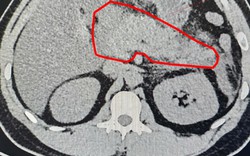

• "Bác sĩ ơi cứu em, nhưng... cho em về ăn Tết xong mổ được không": Lời cầu khẩn khiến bác sĩ khoa Thận-Tiết niệu và Nam học lặng người trước thềm năm mới

"Bác sĩ ơi cứu em, nhưng... cho em về ăn Tết xong mổ được không": Lời cầu khẩn khiến bác sĩ khoa Thận-Tiết niệu và Nam học lặng người trước thềm năm mới

Sức khỏe -

Các bác sĩ cũng nhấn mạnh, người dân không nên trì hoãn điều trị vì bất kỳ lý do nào, kể cả công việc hay chi phí, bởi khi thận đã bị tổn thương nặng, việc điều trị sẽ phức tạp và tốn kém hơn rất nhiều.